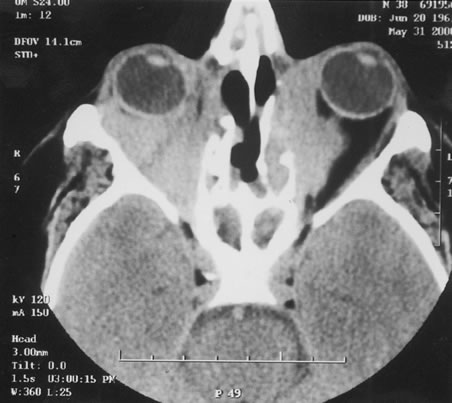

Fig. 6. A. Fundus photograph and B. fluorescein angiogram demonstrating diffuse vaso-occlusive disease in a patient with systemic lupus erythematosus. This is peripheral nonperfusion of the retina. The patient had anticardiolipin antibodies. (Jabs DA, Fine SL, Hochberg MC, et al: Severe retinal vaso-occlusive disease in systemic lupus erythematosus. Arch Ophthalmol 104:558, 1986. Copyrighted 1986, American Medical Association. Reprinted with permission.)